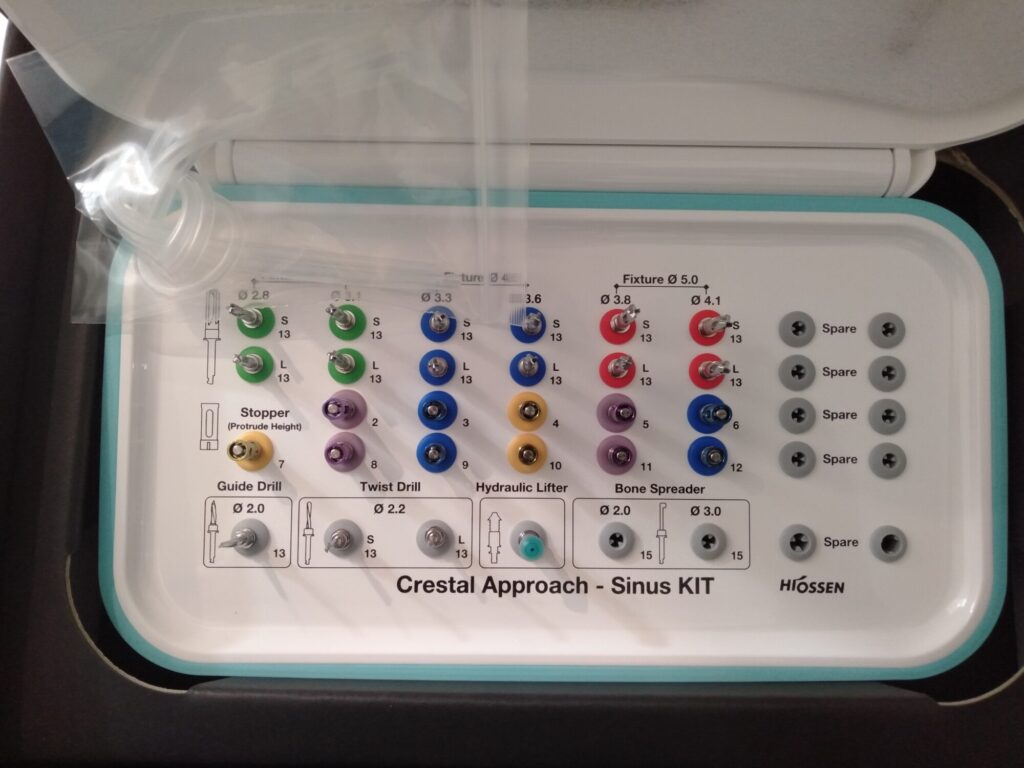

先日、インプラントのオペを行いました。骨が不十分なところに、ソケットリフトという骨造成のテクニックを併用してインプラントを2本埋入しました。

上顎は鼻と近いため、骨が不十分なケースがあります。その場合、鼻と交通している上顎洞という空洞に骨造成してインプラントを埋入します。ソケットリフトは上顎洞に骨造成するテクニックの一つです。骨造成の中では、比較的侵襲の少ないテクニックです。